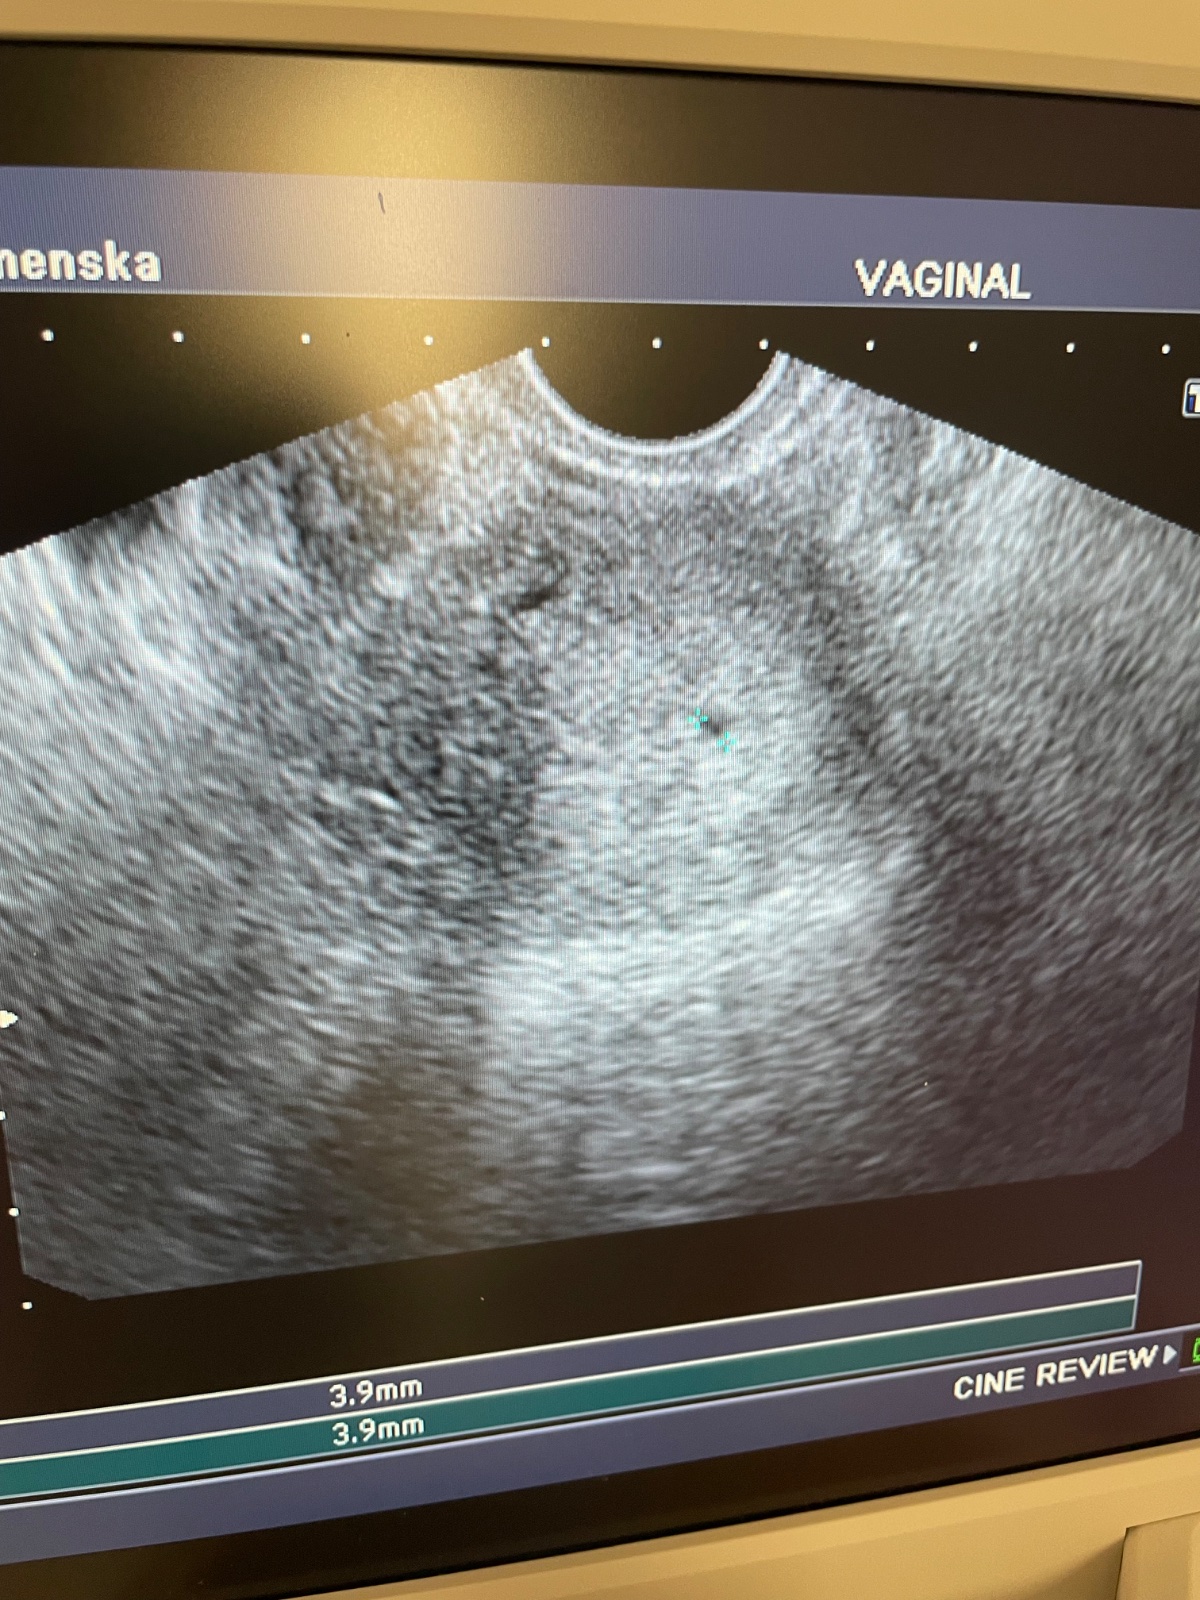

Krásny podvečer ....tak som domka 😊 no zatiaľ nič neviem lekárka mi robila sono ale ešte nič nevidela takže vravela že som menej ako 3 týždne ...zobrala mi krv na hcg a zajtra mám volať o výsledky okolo obeda ....ach to čakanie